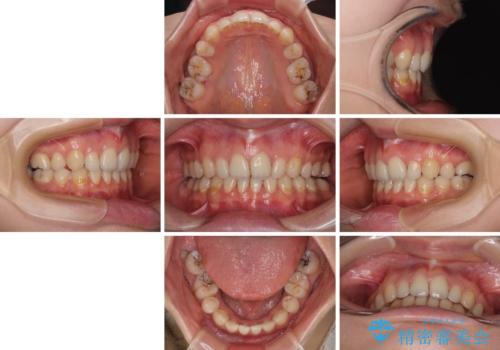

欠損や残存乳歯、深い咬み合わせ ワイヤー矯正で咬合改善

甚大な咬合力に抵抗して過蓋咬合を改善する必要があり、更には口元が引っ込みすぎることがないように仕上げていく必要もあったため、治療期間は3年を超えましたが、当初計画通りの仕上がりで治療を終えることができました。